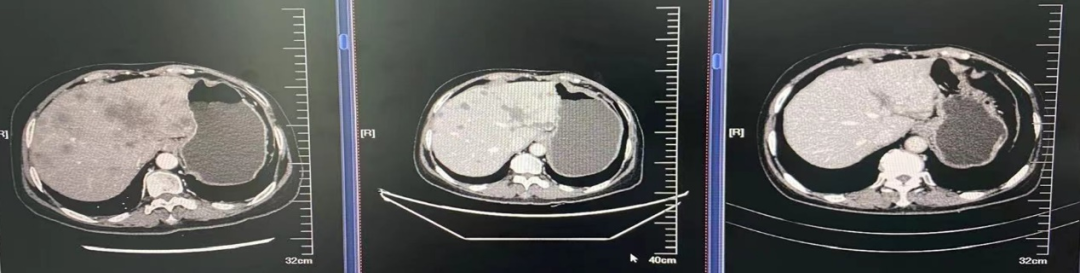

▌影像学检查:

图4.肺窗

2021年4月7日双肺示:转移可能。